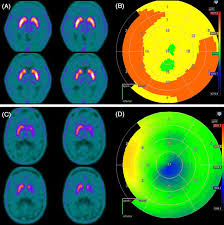

An F-DOPA PET scan is a specialized imaging test used to evaluate dopamine activity in the brain. It is most commonly recommended to diagnose conditions like Parkinson’s disease, movement disorders, certain brain tumors, and other neurological concerns. Because F-DOPA imaging provides highly detailed insights into brain function, it’s essential to get this test done at the Best F-DOPA PET Scan Center Near Me where accuracy and expertise are guaranteed.

A quality diagnostic center ensures that the tracer is handled properly, the imaging is performed correctly, and the interpretation of results is done by a skilled nuclear medicine specialist.